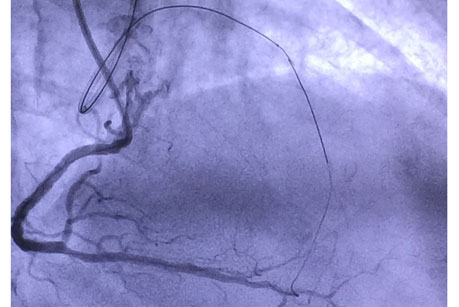

患者女性,78岁,因冠状动脉粥样硬化性心脏病,急性下壁心肌梗死,陈旧前壁心肌梗死入院。入院后完善冠脉造影术示:三支血管病变,左前降支近端100%闭塞;回旋支近端70-80%节段性狭窄;右冠近至远端70-80%弥漫性狭窄,后降支90%狭窄。患者病变严重,前降支为CTO。赵慧强主任详细阅片并查看患者后,决定为患者行血运重建治疗。

手术在11月6日进行,由赵慧强主任、张文广副主任医师担任术者。手术穿刺了两侧的桡动脉,均置入指引导管,微导管支持下送入前向导丝拟开通CTO病变,但闭塞病变处严重钙化,经尝试不能通过闭塞段到达远端真腔。鉴于右冠向左前降支发出良好的侧枝循环,此时果断地采用逆向导丝技术,首先干预右冠近端及远端病变,搬开逆向导丝应用的“绊脚石”,在微导管支持下专用导丝依次通过右冠后降支→侧枝循环→间隔支→前降支闭塞病变远端,逆行进入前降支闭塞病变远端,但逆向微导管未能送入侧枝内,遂改变策略再反复调整前向导丝前进,最终前向导丝与逆向导丝“抱紧”,成功通过闭塞病变到达前降支远端病变真腔,顺利完成支架置入。术后患者未再发作胸憋、胸痛,已顺利出院。